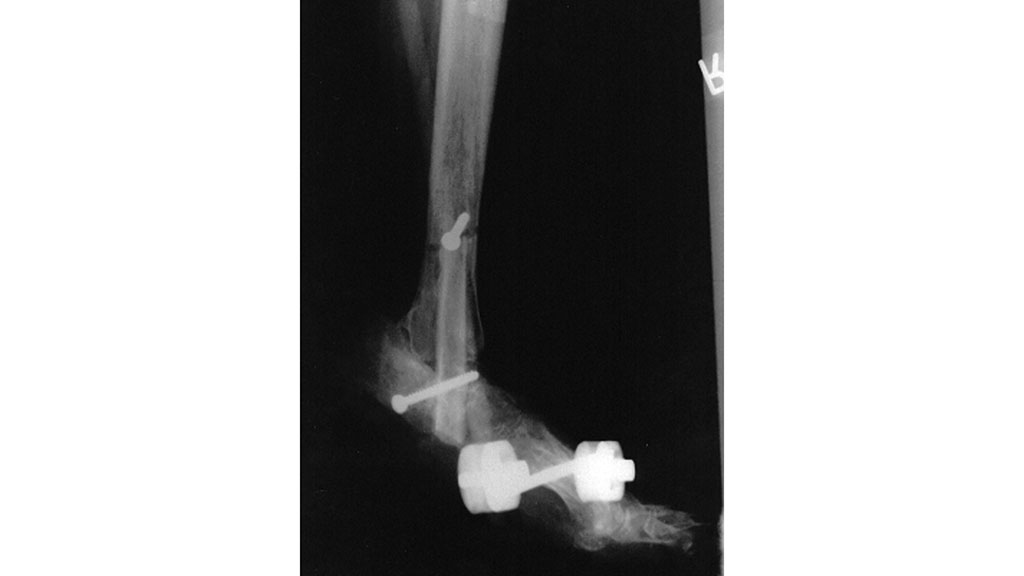

Ebenso werden die diabetogen bedingten Veränderungen im Bereich der Sehnen im Zusammenspiel zwischen Agonisten/Antagonisten, augenscheinlich insbesondere bei den Streck- und Beugesehnen im Zehenbereich (Krallenzehe, Hammerzehe, Halluxvalgus etc.), aber auch die unter besonderer statischer Belastung stehende Achillessehne und Tibialis-anterior-Sehne überhaupt nicht mitbetrachtet. Bezüglich ihrer Pathomorphologie besteht oft völlige Unkenntnis über Funktionsstörungen durch die zunehmende Rigidität oder Schrumpfung unter der diabetogenen Stoffwechselsituation, die dann zu Fußform- und Druckveränderungen (im Sinne des Knick-Klump-Sichelfußes u. a.) führen können (Abb. 2 u. 3).

Sind beim diabetischen Fuß Fußverformungen eingetreten, die zu einer erheblichen punktuellen Druckbelastung („Intrinsic“) und der Ausbildung von Druckgeschwüren geführt haben, so sind diese im Rahmen der Leitlinienempfehlungen beim diabetischen Fuß bis vor Kurzem noch durch eine Amputation gefährdet gewesen, insbesondere dann, wenn durch eine Infektion im Zehenbereich (Abb. 5), durch einen freiliegenden Knochen oder ein freiliegendes Gelenk die Heilungsmöglichkeiten eingeschränkt waren. Diese Vorgehensweise ist in vielen Fällen nicht mehr notwendig. Durch minimalinvasive chirurgische Eingriffe lassen sich die Fehlstellungen der Zehen und die dadurch bedingte Fehlbelastung korrigieren. Im Ergebnis heilen Ulzerationen spontan ab. Gleichzeitig ist hierbei eine schuhtechnische Druckentlastung erforderlich. Selbst bei entzündlicher Beteiligung der Knochen (Osteomyelitis/Ostitis) lässt sich durch chirurgische Ausräumung des krankhaften Befundes am Knochen kombiniert mit der Einlage von Septopalketten und Stabilisierungsmaßnahmen (Bohrdraht) der Infekt bekämpfen.